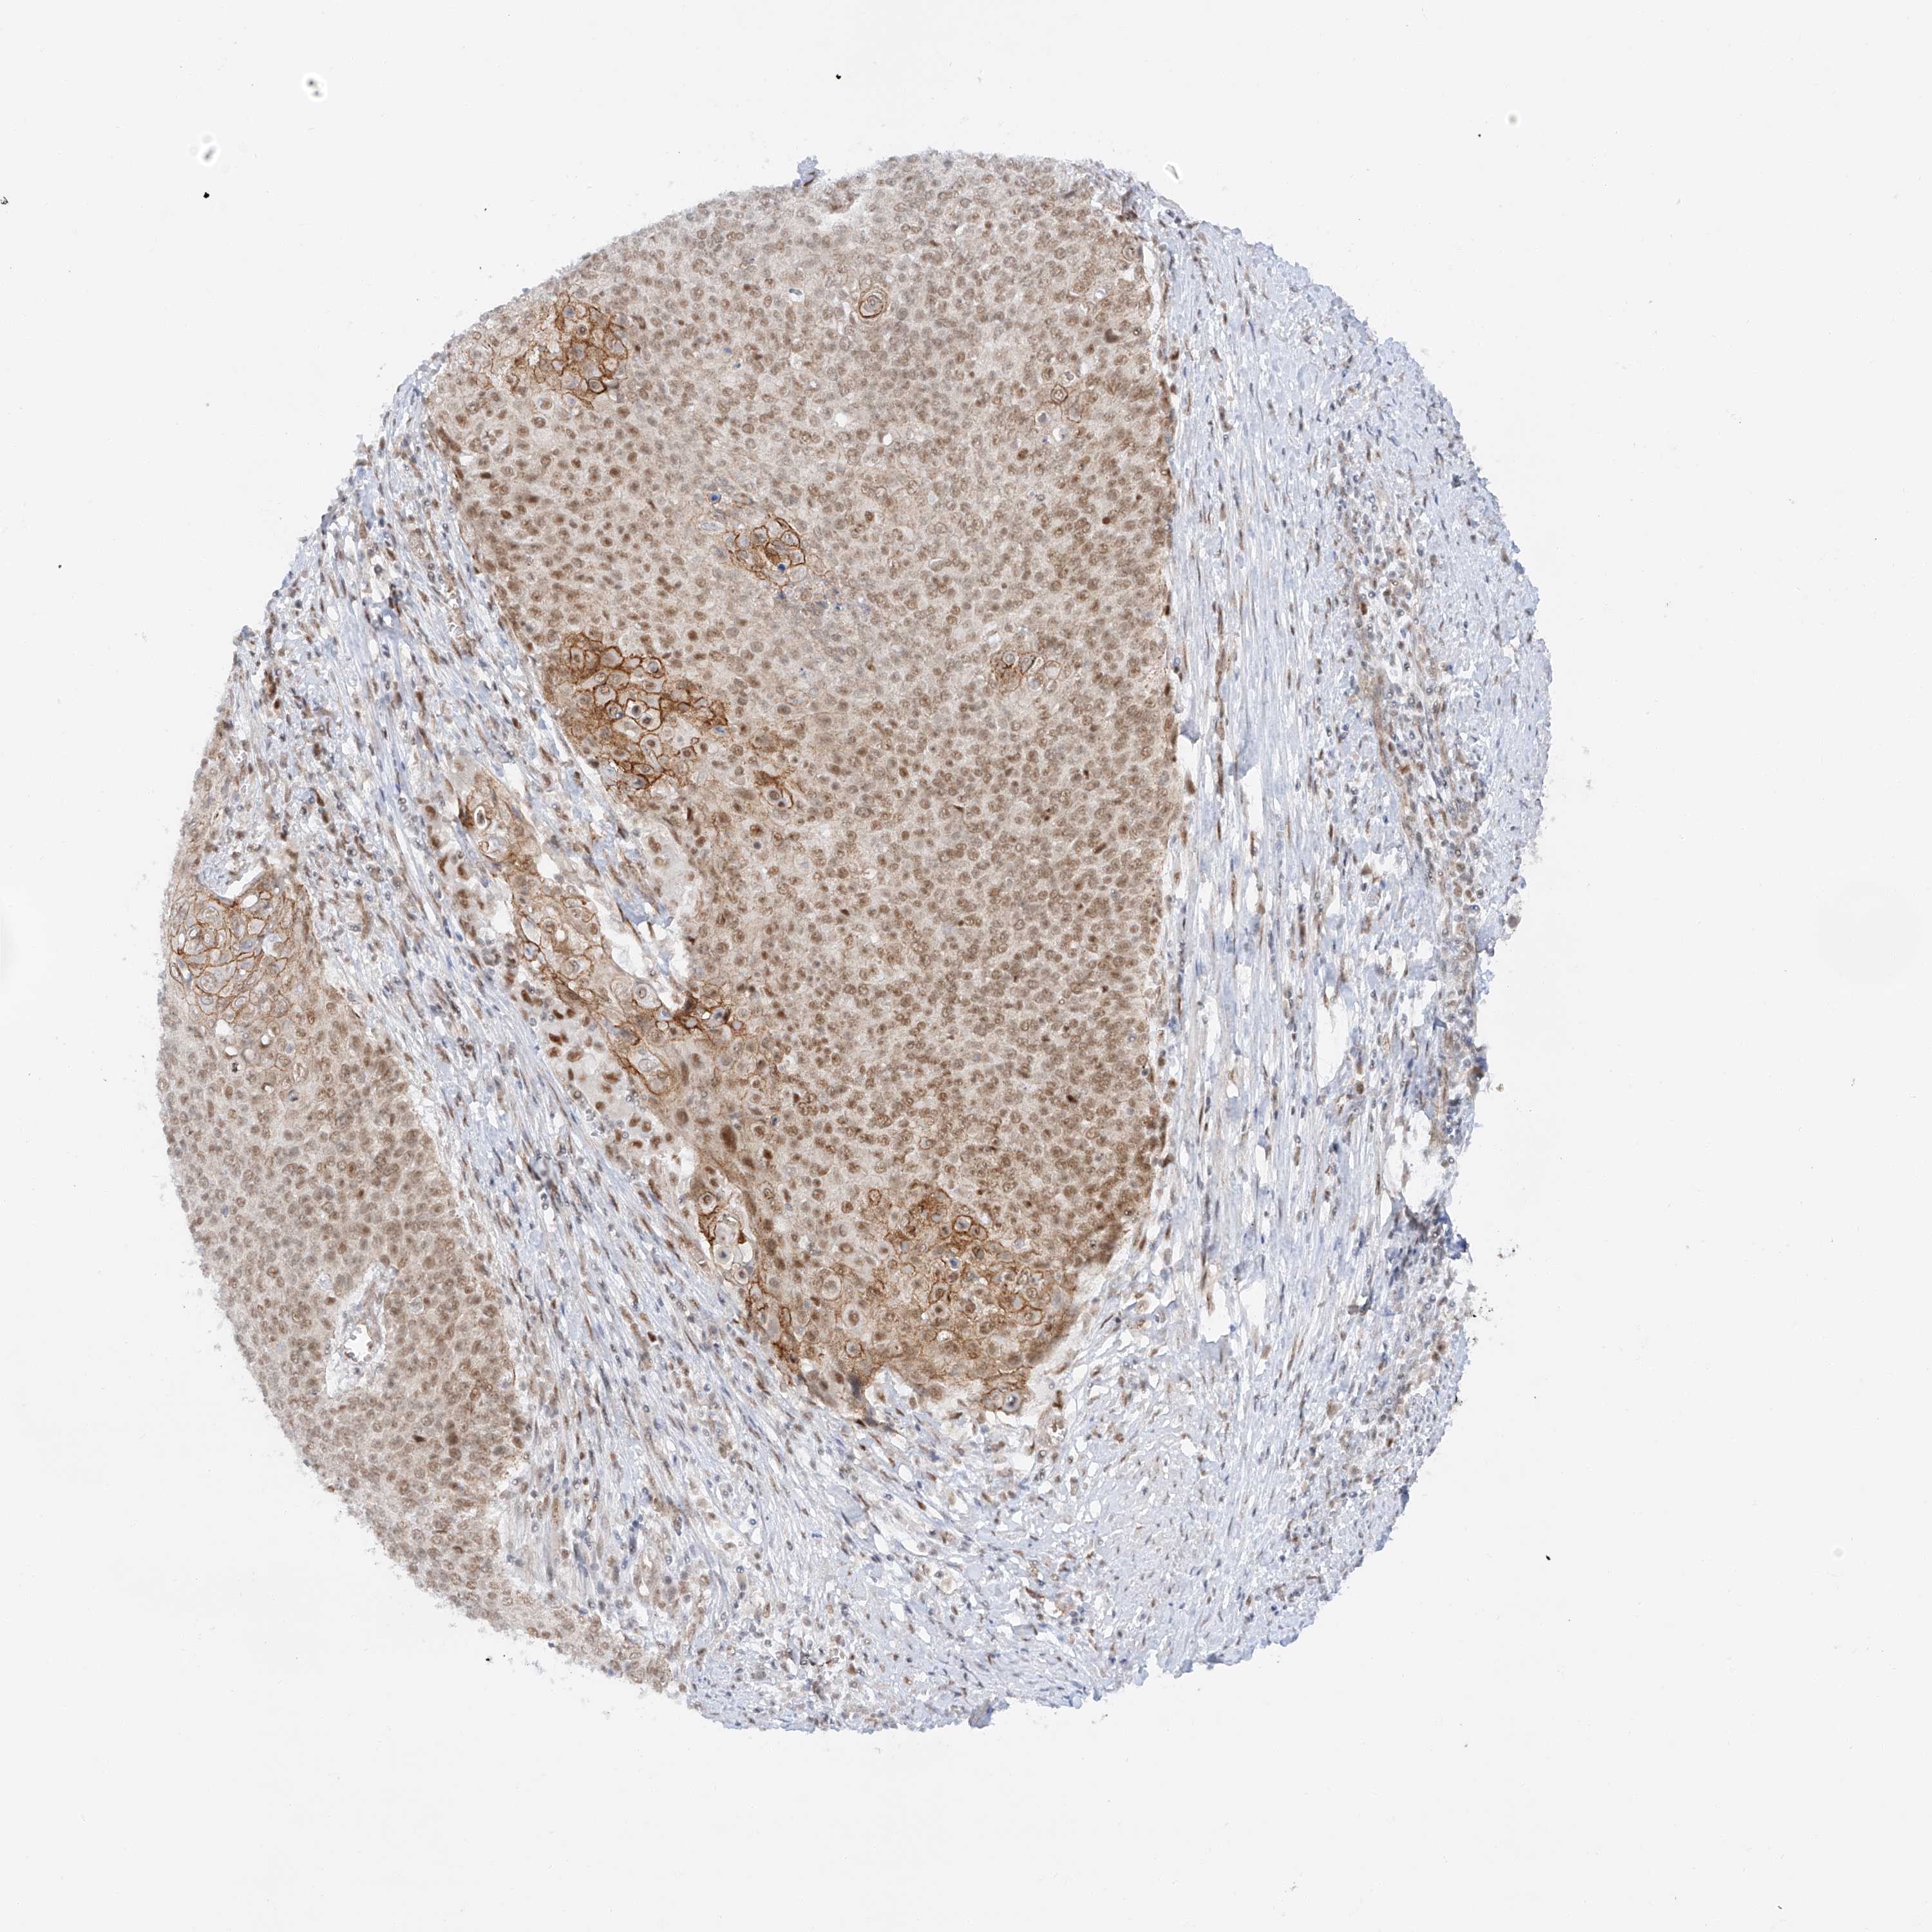

CERVICAL CANCER - Protein expressioni

A mouse-over function shows sample information and annotation data. Click on an image to view it in a full screen mode. Samples can be filtered based on level of antibody staining by selecting one or several of the following categories: high, medium, low and not detected. The assay and annotation is described here.

Note that samples used for immunohistochemistry by the Human Protein Atlas do not correspond to samples in the TCGA dataset.

Antibody stainingi

Antibody staining in the annotated cell types in the current human tissue is reported as not detected, low, medium, or high, based on conventional immunohistochemistry profiling in selected tissues. This score is based on the combination of the staining intensity and fraction of stained cells.

Each image is clickable and will lead to virtual microscopy that enables deeper exploration of all samples and also displays staining intensity scores, fraction scores and subcellular localization as well as patient and tissue information for each sample.

Antibody HPA031630

Staining

High

Medium

Low

Not detected

Intensity

Strong

Moderate

Weak

Negative

Quantity

>75%

75%-25%

<25%

None

Location

Nuclear

Cytoplasmic/membranous

Cytoplasmic/membranous,nuclear

Squamous cell carcinoma, NOS

Adenocarcinoma, NOS